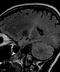

In 2013, Wagers and Lee showed that GDF11 tightened hypertrophic mouse hearts, restoring efficiency. This year, Wagers and Rubin published two separate Science papers finding GDF11, in the equivalent of “70-year-old” mice, rejuvenated muscles enough to improve exercise capacity, and rejuvenated brain neurons and blood vessels well enough to improve sense of smell.

Cells affected are sometimes multipotent stem cells, sometimes not. “The heart remodeling involved no stem cells,” Wagers said. “Adult cardiomyocytes changed their size. Terminally differentiated satellite muscle cells underwent a remodeling of their structural integrity. In the brain, neural stem cells expanded. But we don’t think stem cells were involved in remodeling the blood vasculature.”